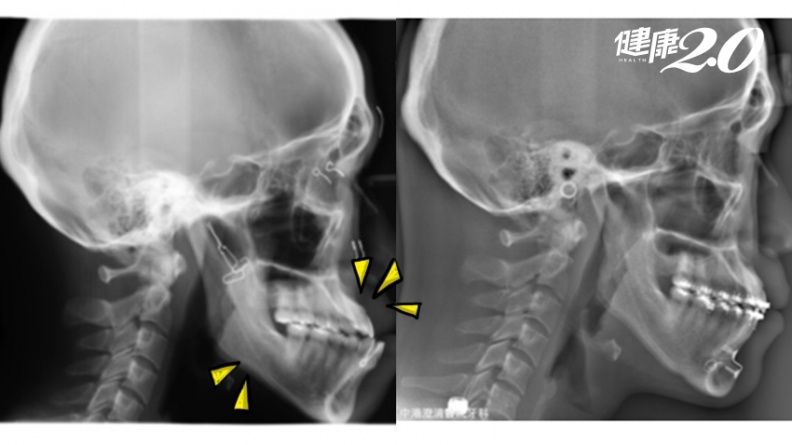

▲ 王同學接受治療前下顎內縮、嚴重暴牙(圖左);經過齒列矯正治療、重建顳顎關節與正顎手術後外觀明顯改善(圖右)。

針對王同學的病況,因為暴牙導致下顎後縮且歪斜、牙齒咬合不良,醫師評估後先為她進行齒列矯正治療及重建顳顎關節,先打好基礎,待骨頭發育成熟後,再進行正顎手術。雖然治療過程漫長,術後至今2年仍需配戴維持器,但王同學開心地說,現在不像以前總是睡睡醒醒,終於可以睡得好了。